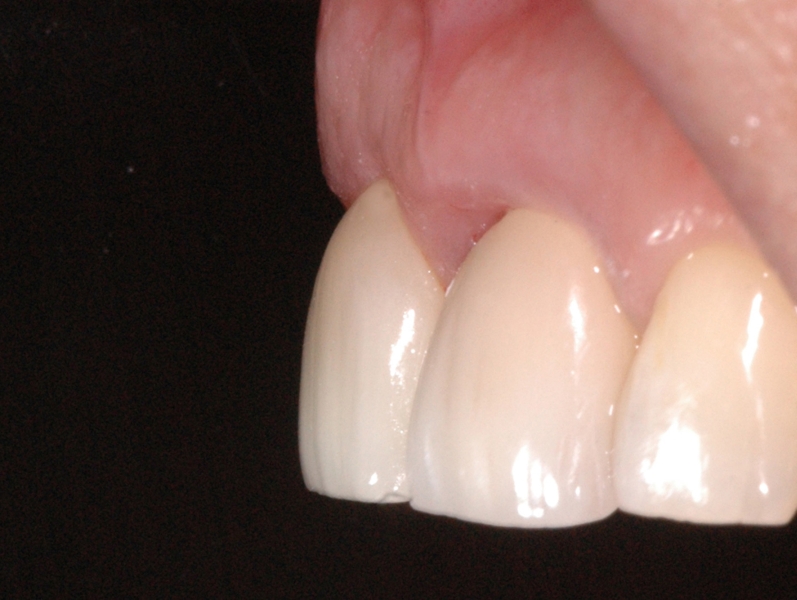

2/18 - Obvious loss of the buccal lamellaGBR together with soft tissue augmentation with mucoderm® and maxresorb® - Dr. S. Scherg